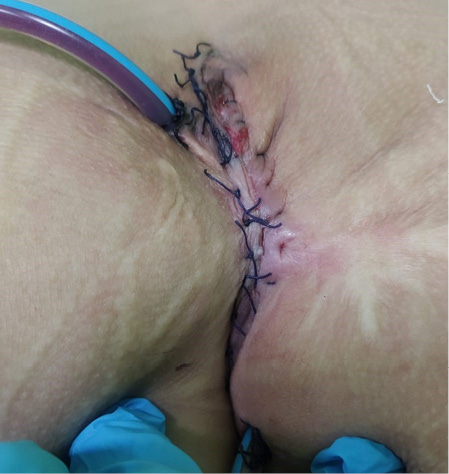

Выполнено иссечение пресакральной кисты с резекцией копчика, дренирование пресакрального пространства. Ребенок уложен в положение на животе для заднесагиттального доступа. Разрезом по межъягодичной складке с захватом имеющихся заранее прокрашенных бриллиантовой зеленью свищевых ходов послойно начато выделение конгломерата кист в пресакральном пространстве. Выполнена резекция двух последних позвонков, после чего кисты единым блоком выделены из значительных по массивности рубцовых тканей с контролем задней стенки прямой кишки, которую удалось сохранить в целостности. При выделении позади копчика одна из кист вскрылась, выделилось до 10 мл густого гноя с колибациллярным запахом (взят посев). Тем не менее кисты выделились из окружающих тканей единым блоком. Задняя стенка прямой кишки — без повреждений. В области резецированного копчика уложена пластина тахокомб. Далее получившееся пространство с явно несводимыми стенками дренировано силиконовым дренажом через контрапертуры по обеим сторонам кожного разреза для налаживания в последующем системы отрицательного давления. Далее выполнено послойное ушивание рассеченных мышц тазового дна. Рана послойно ушита наглухо (рис. 9).

Рисунок 9.

Вид послеоперационной раны

Figure 9.

Type of postoperative wound

Лечение послеоперационной раны проводили с использованием аппарата отрицательного давления, наложением вакуум-ассистированной повязки в течение 8 послеоперационных суток. После удаления дренажа отмечалось скудное серозное отделяемое из послеоперационной раны. Проводили физиотерапевтическое лечение послеоперационной раны с целью заживления послеоперационного шва — воздействие коротким ультрафиолетовым излучением и поляризованным светом.

По данным контрольного ультразвукового исследования, на 10-е послеоперационные сутки в крестцово-копчиковой области вдоль послеоперационного шва дополнительные образования достоверно не визуализировались. Ребенок выписан домой на 13-е послеоперационные сутки. В течение месяца после выписки отмечалось скудное серозное отделяемое через вторично заживающую часть послеоперационной раны. Через 3 месяца отмечается полное заживление раны, активных жалоб не предъявляет (рис. 10). Длительность катамнестического наблюдения составила 2 года.

Рисунок 10.

Вид послеоперационной раны через 3 месяца

Figure 10.

Type of postoperative wound in 3 months